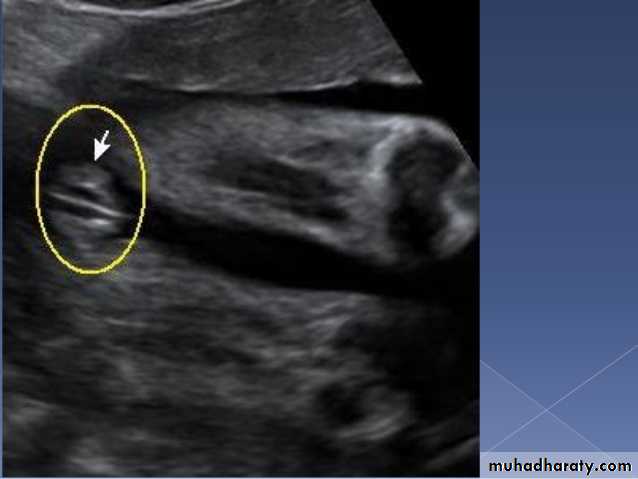

Blighted ovum

Anembryonic pregnancy is a form of a failed early pregnancy, where a gestational sac develops, but the embryo does not form. The term blighted ovum is synonymous with this, but is falling out of favour and is best avoided.Radiographic features

Ultrasound

An anembryonic pregnancy may be diagnosed when there is no fetal pole identified on endovaginal scanning , and:the size of the gestational sac is such that a fetal pole should be seen: MSD ≥25 mm on TVS (by RCOG criteria)